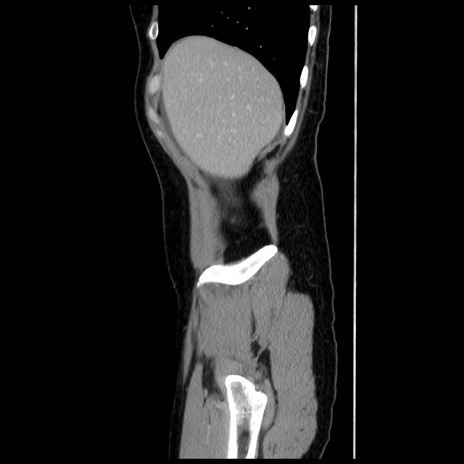

横断像

【症例】 50歳代女性

【主訴】 腹痛

【現病歴】前日生レバーを食べた。今朝に排便あり。 昼前に突然発症の腹痛を生じ、当院救急外来を受診した。

【既往歴】 子宮筋腫にてで子宮全摘後

【身体所見】 意識清明、腹部:平坦、軟、下腹部やや左を中心に圧痛・反跳痛あり、筋性防御あり

【データ】WBC 7800、CRP 0.07